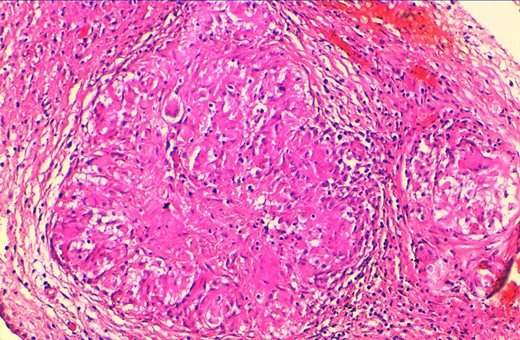

A substantial proportion of women’s specimens were addressed for histopathological analysis for malignant suspicion on clinical examination and on imaging techniques (seven cases, 53.84%). These patients presented with abnormal bleeding (especially metrorrhagia in older patients) or with mass-forming lesions on clinical examination and on imaging techniques. Diverse surgical procedures were performed on eight cases (61.53%). Most patients had multifocal FGTB (9 cases, 69.23%) with extragenital involvement especially peritoneal or lymph node locations (five and two cases respectively). The most involved genital organs (whether solely or with other organs) were fallopian tubes (63.84%), ovaries (46.15%), endometrium (38.46%) and the cervix (23.07%). The patient No-8 had a concomitant cervical adenocarcinoma. The macroscopic aspects of all resected specimens did not show the classic cheese-like appearance of the caseous necrosis (Fig. 1), rather they show morphologic abnormalities (distended fallopian tubes, hard endometrium), haemorrhage, cystic changes or ischaemic necrosis. The histopathological analysis showed granulomatous lesions associated with variable amount of caseous necrosis (Figs 2 and 3). All patients were HIV-negative, they received the standard antibiotic therapy (combination of rifampicin, isoniazid, ethambutol and pyrazinamide).

Histological view showing ovarian parenchyma with granulomatous lesions and caseous necrosis (H&E × 100).

At higher magnification, tuberculosis granulomas include epithelioid and giant cells, plasma cells and caseous necrosis, along with fibrotic changes (H&E × 200).